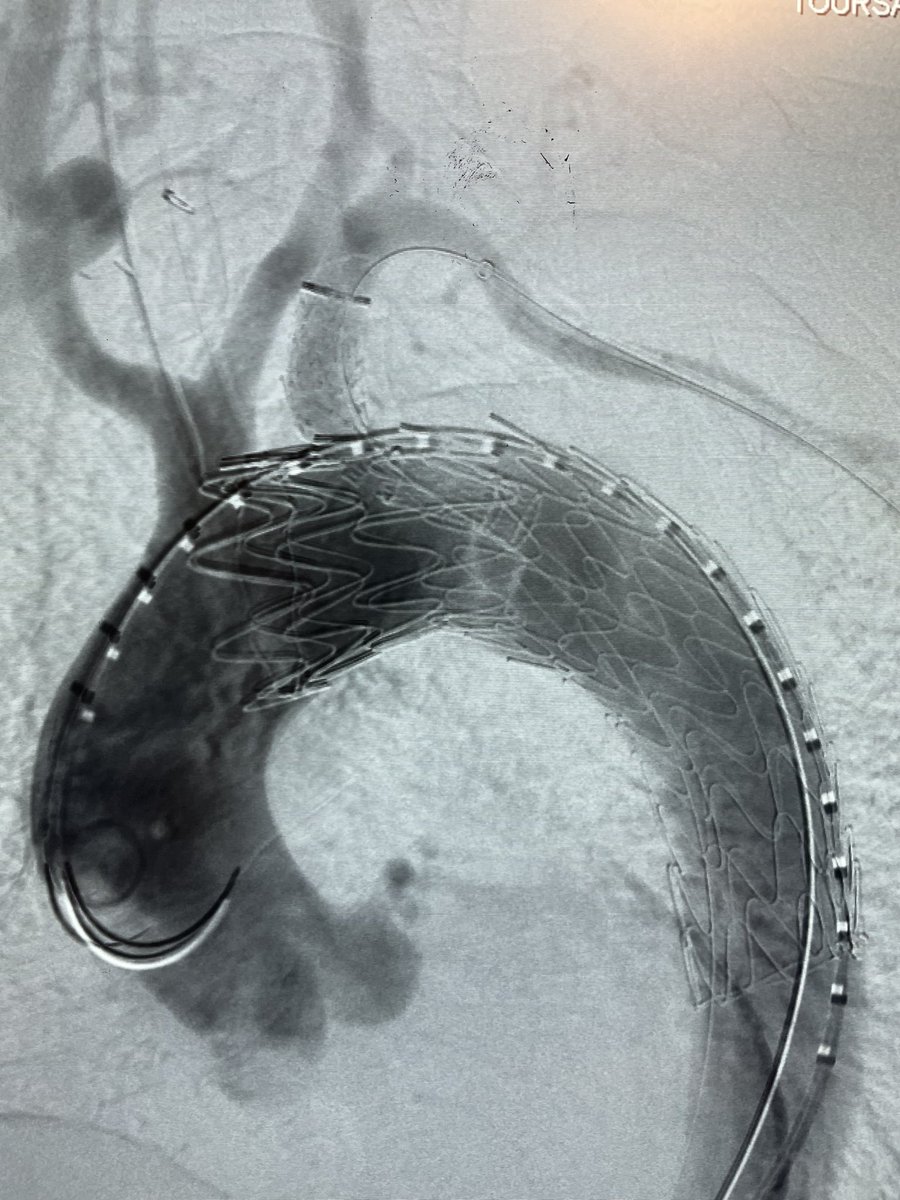

Great outcome using GORE TBE in an emergency case with replaced right SCA and zone 3 contained rupture PAU. Thanks to collaboration of Vascular and Cardiac surgery team. @MarylandSurg @UMMC The first commercial use of TBE in Maryland

@SToutsavadkohi @dr_ghoreishi @BtaylorMD2